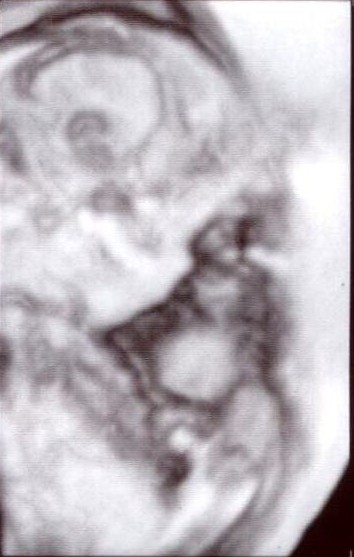

This was at 12 weeks. Image Attachment(s):

This was at 12 weeks.